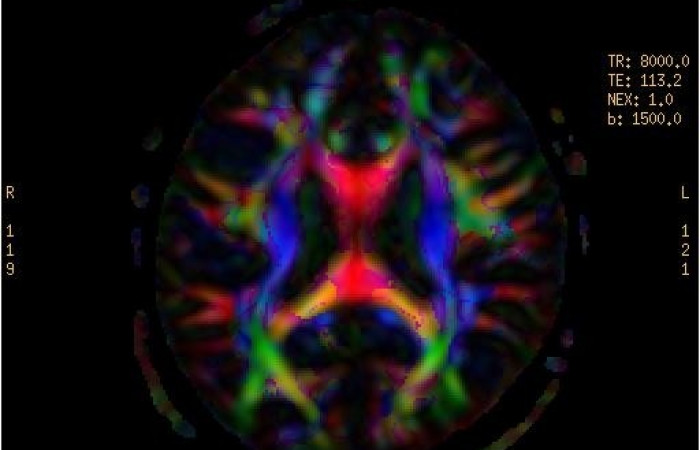

ˇ badanie dyfuzyjne mózgu z traktografią

- Dyfuzja MR z traktografią pozwalającą na prezentację dróg nerwowych